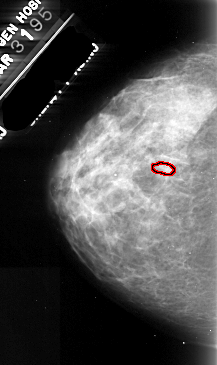

A_1105_1.LEFT_CC

LEFT_CC LINES 4741 PIXELS_PER_LINE 2821 BITS_PER_PIXEL 16 RESOLUTION 42 OVERLAY

FILE: A_1105_1.LEFT_CC.OVERLAY

TOTAL_ABNORMALITIES 1

ABNORMALITY 1

LESION_TYPE CALCIFICATION TYPE PLEOMORPHIC DISTRIBUTION CLUSTERED

ASSESSMENT 4

SUBTLETY 2

PATHOLOGY MALIGNANT

TOTAL_OUTLINES 1

BOUNDARY